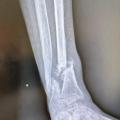

• les interventions prothétiques non conservatrices (fig. 1).

• l’ostéosynthèse consistant en une réduc­tion directe ou indirecte de la fracture, puis en son immobilisation par du matériel intra-osseux (broche, clous, vis, plaques), ou parfois à l’extérieur du membre (fixateur externe), notamment en cas de fracture ouverte grave (fig. 2). Une immobilisation complémentaire par attelle ou plâtre peut être associée.

L’évolution normale d’une fracture conduit à sa consolidation et au rétablissement de la fonction du membre. Cette évolution peut être compliquée par un déplacement secondaire, un retard de consolidation, une non-consoli­dation (pseudarthrose) ou une consolidation non anatomique (cal vicieux) [fig. 3], pouvant nécessiter des chirurgies complémentaires.